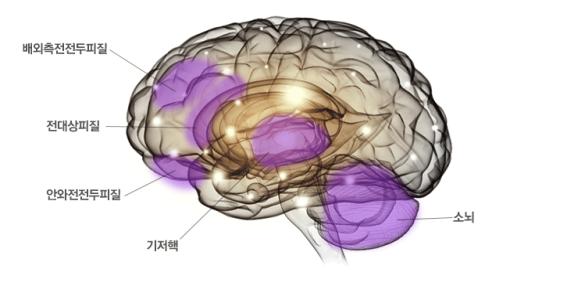

1. 인지조절(cognitive control) 네트워크이다.

배외측 전전두피질, 안와 전전두피질, 전대상피질, 기저핵, 소뇌 등이 이 네트워크에 해당되는데, 각성하고, 주의집중하고, 정보를 처리하고, 충동을 억제하는 등의 기능을 담당한다. 즉, 우리가 흔히 무언가에 집중해서 생각할 때 이 네트워크가 활성화된다.

따라서 집중력 저하가 가장 큰 특징인 ADHD에서는 이 네트워크의 기능이 저하되는 소견을 보인다.